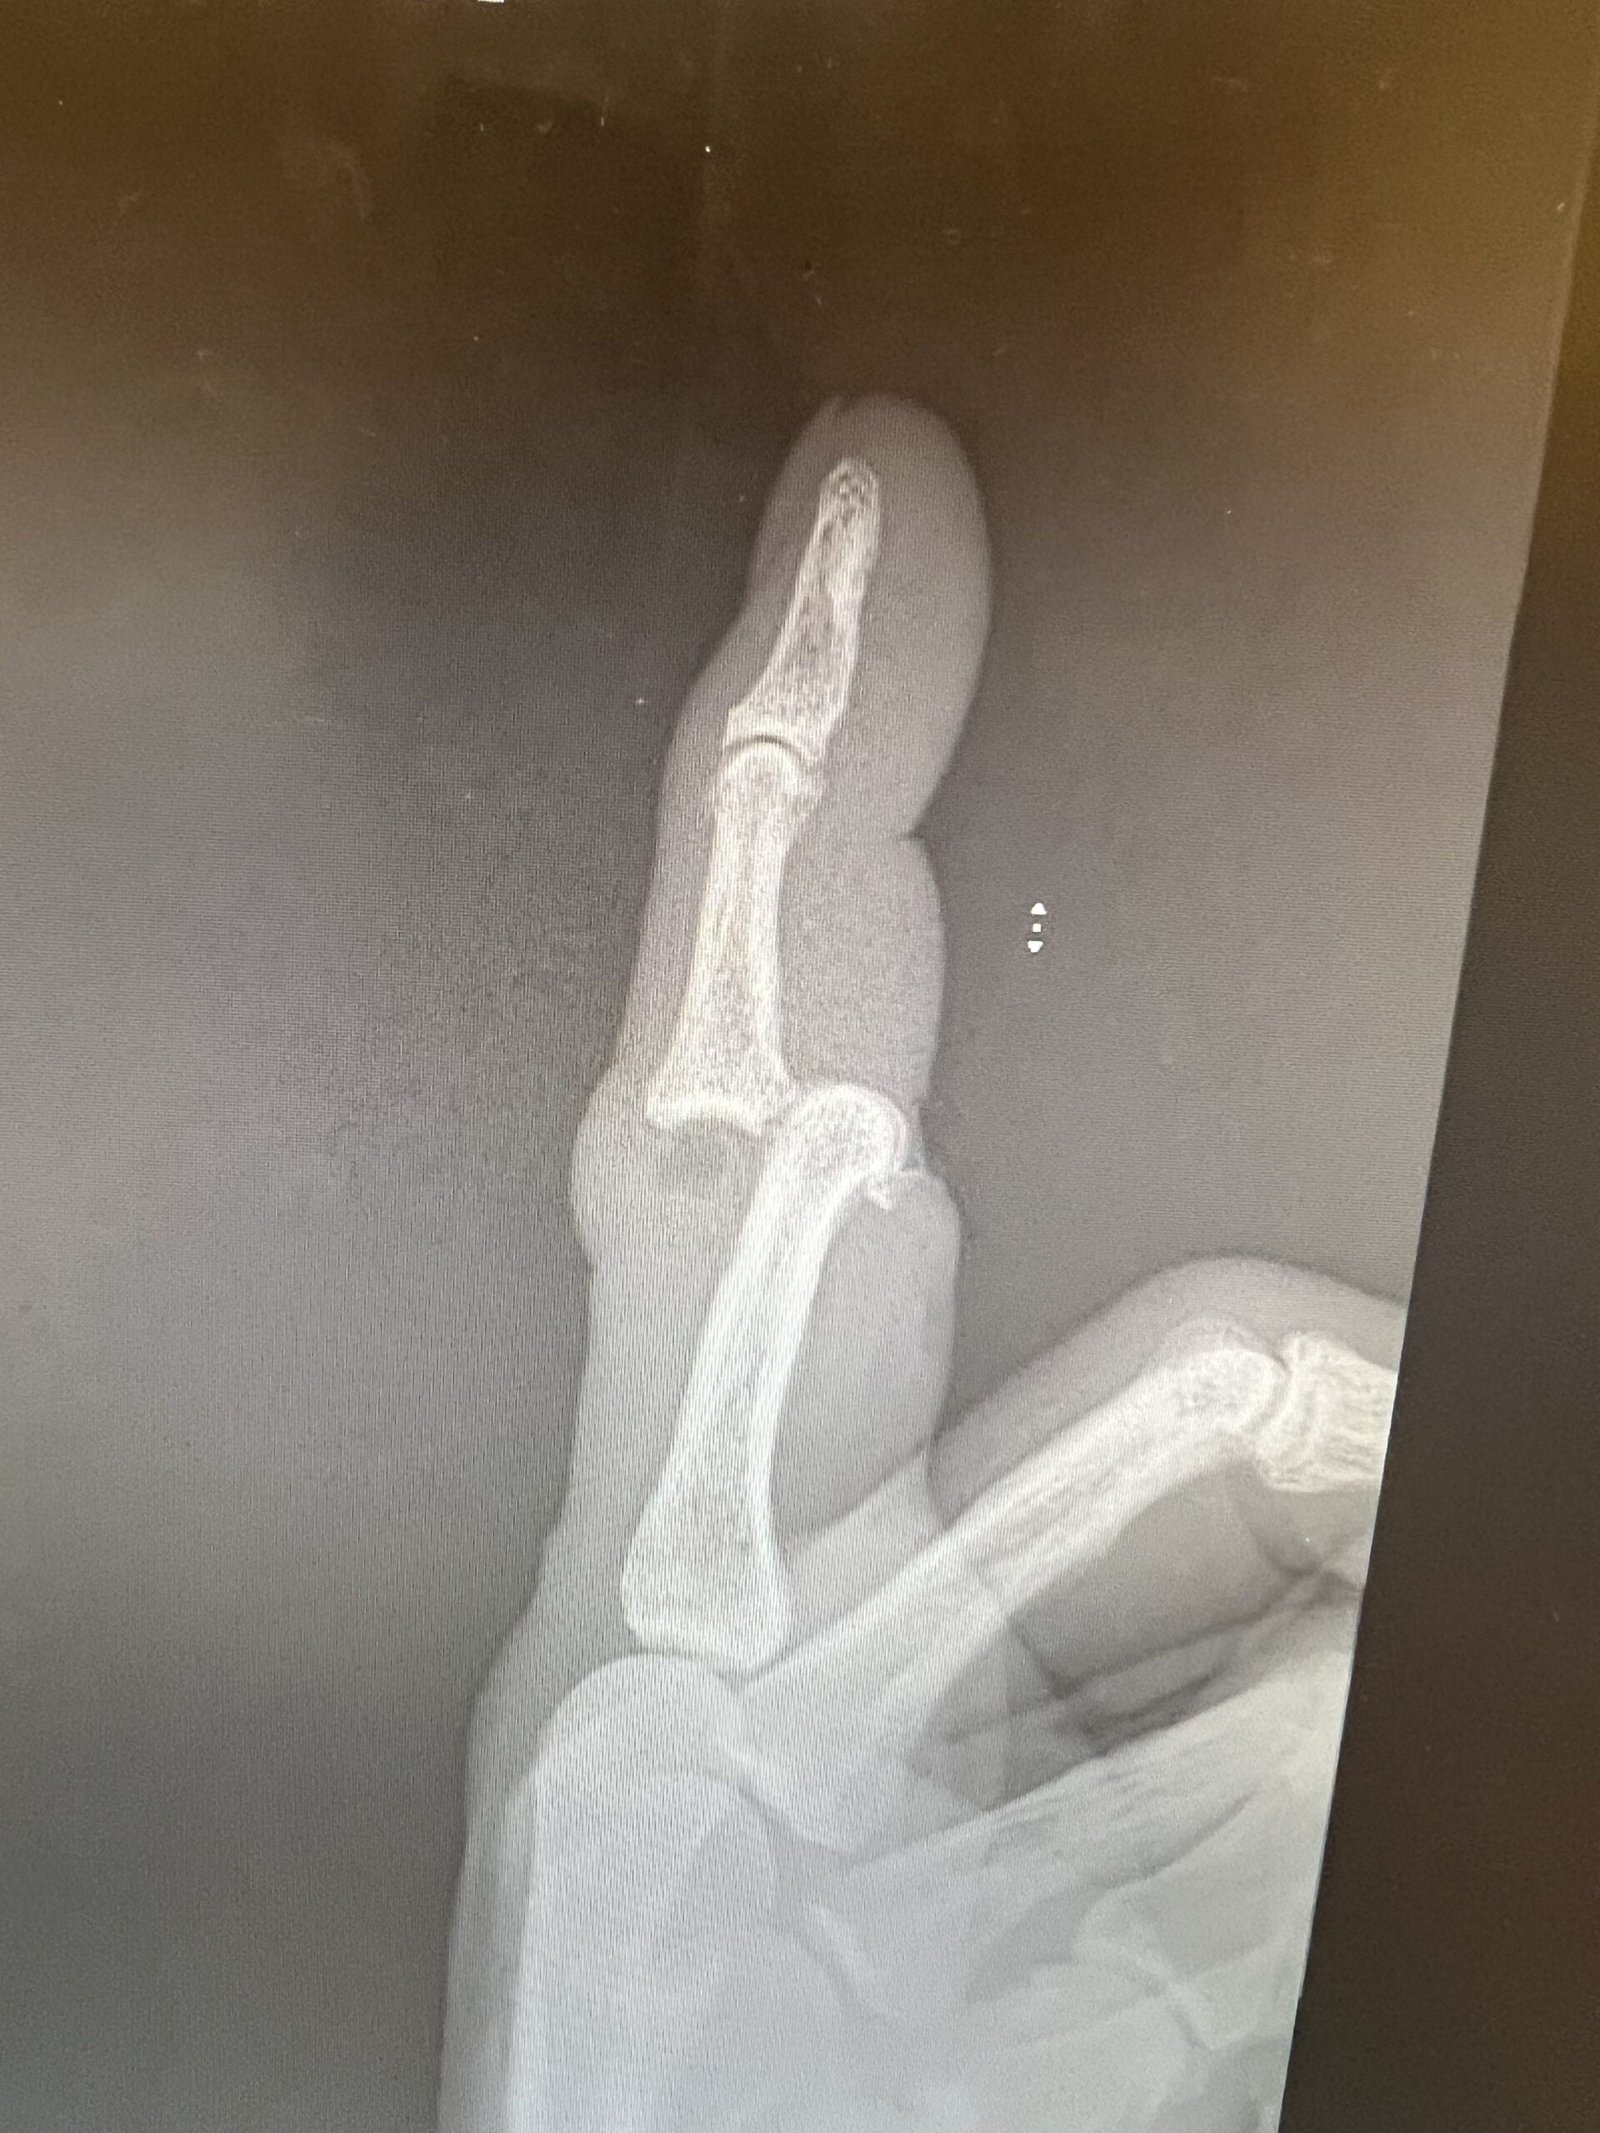

- Radiology

- TX: pull on it and splint